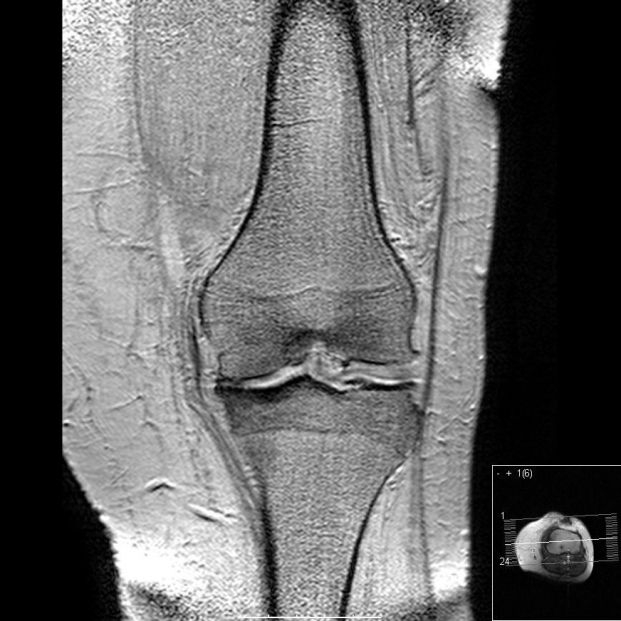

Nuevo análisis de sangre más preciso para identificar la progresión de la artrosis de rodilla

Investigadores estadounidenses avanzan en el estudio de la artrósis de rodilla desarrollando un nuevo análisis de sangre más eficaz que los procedimientos anteriores, según publican los investigadores en la revista 'Science Advances'.

Recordemos que la artrosis es una enfermedad degenerativa articular que provoca la destrucción del cartílago que recubre los huesos. Esta enfermedad carece en la actualidad de tratamientos eficaces para su tratamiento y resulta complicado pronosticar su avance.